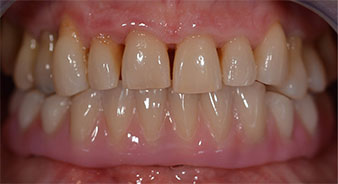

Направи се скенер с триизмерна компютърна томография (CBCT, Planmeca), за да се подпомогне планирането и да се намалят рисковете. Той показа, че качеството и количеството на наличната кост са достатъчни за операцията и имедиатното възстановяване, използвайки Fast & Fixed метод. Следвайки протокола за тази концепция, имплантите са поставени на 35, 32, 42 и 45 позиция. Ангулирането на дисталните импланти до 45° промени профила в задната зона и осигури по-голяма поддръжка в многоъгълната зона (Фиг. 3).

Fast & Fixed метод

Фиг. 3